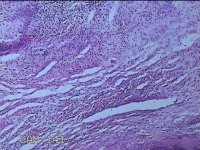

双侧肩锁关节处肿物

性别

女

年龄

30岁

临床诊断

纤维瘤病

一般病史

无

标本名称

大体所见

灰白暗红色肿物2x1.3x0.8cm两个,表面糜烂,切开肿物呈实性,切面灰白粉红色,质软。